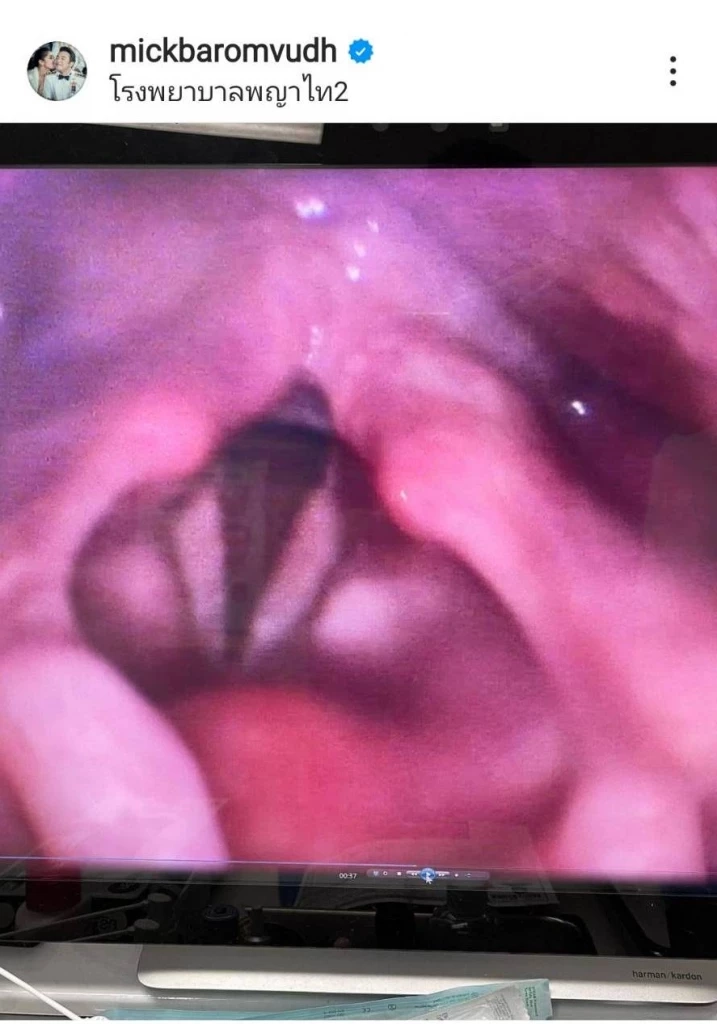

"จนได้!! เส้นเสียงอักเสบและบวมมาก ไม่มีเสียงเลย หมอให้งดใช้เสียง 1 อาทิตย์นะครับ ขอโทษงานทุกงานที่ต้องขอเลื่อนออกไปนะครับ และถ้ามีอะไรติดต่อพี่ตูนได้เลยครับผม แต่เรานี่ซิห้ามใช้เสียง 1 อาทิตย์ น่าจะชักดิ้นชักงอเองก่อนแน่เลย เถียงภรรยาก็ไม่ได้ โอ๊ยยยยยยยยยย !!!!!"

ถึงจะงดใช้เสียงแต่ก็ยังอดไม่ได้ขอแซวศรีภรรยา “เบนซ์ พรชิตา” เสียหน่อย ตามสไตล์หนุ่มอารมณ์ดีอ่ะแหละ ดูท่า “หนุ่มมิค” คงจะอึดอัดน่าดู เพราะปกติก็เป็นคนคุยเก่ง สนุกสนานเฟรนด์ลี่เป็นทุนเดิม แต่อย่างไรก็ตามคงต้องปฏิบัติตามที่คุณหมอสั่งอย่างเคร่งครัด นอกจากนี้ เจ้าตัวยังได้โพสต์รูปบริเวณภายในลำคอให้เห็นว่าบวมและแดงอีกด้วย